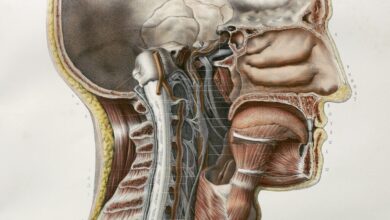

Health NetherlandsResearchers Might Have Found the First New Human Organ in 300 Years

A team of researchers from the Netherlands believe they have identified a new pair of large salivary glands where the nasal cavity meets the throat. If confirmed, it could be the first identification of its kind in 300 years.